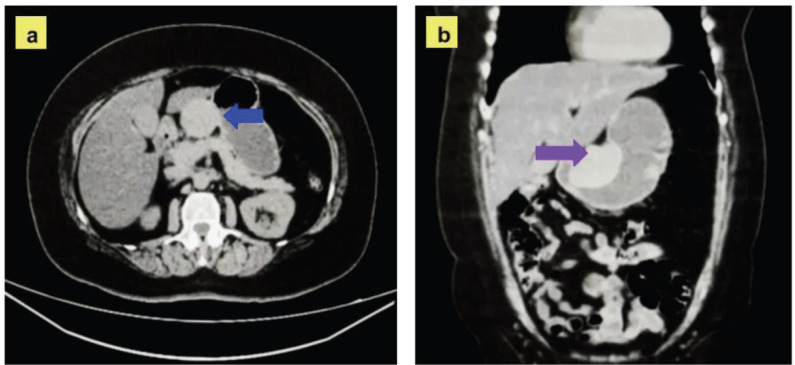

Gastric schwannomas (GS) are rare tumours originating from Schwann cells that affect the gastrointestinal tract, posing a diagnostic challenge due to their nonspecific symptoms. We report the case of a 61-year-old female presented with gastric fullness and occasional episodes of abdominal pain. Computed tomography revealed a solid mass in the lesser curvature of the stomach, initially suspected to be a gastrointestinal stromal tumours. During surgery, an exophytic lesion was identified and confirmed histopathologically and immunohistochemically as a gastric schwannoma. GS should be considered in the differential diagnosis of gastric subepithelial tumours. Its diagnosis relies on immunohistochemistry, and surgical resection ensures effective treatment.